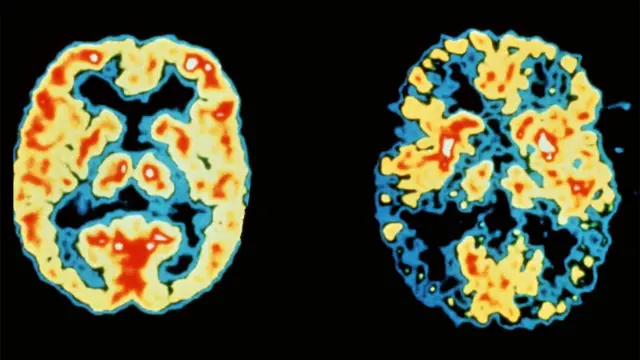

Cudurka Dementia, (Qasaas) oo ay ku jiraan cudurka Alzheimer ayaa noqday dilaaga ugu wayn ee England iyo Wales ee Britain, isagoo ka hormaray wadno xanuunka, sida ay sheegtay tiradii ugu danbaysay ee soo baxday.

Xafiiska Tirikoobka Qaranka ( Office for National Statistics ), ayaa sheegay in isbadalka ay badankeed u badan tahay inay keentay dadka oo waqti dheer noolaanaya, iyo dhaqaatiirta oo horumar ka gaaray inay helaan cudurka.

Sanadkii hore, in ka badan 61,000 oo qof ayaa u dhintay dementia taasoo ah 11.6% dhimashada la diiwaan galiyay.

Cudurada Dementia iyo Alzheimer ayaa u dhigma 15.2% dhimashada haweenka, iyadoo ahayd 13.4% sanadkii 2014.